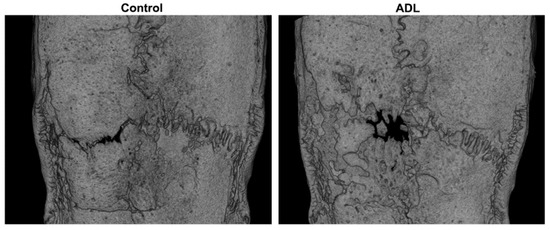

3.2. µCT Analysis